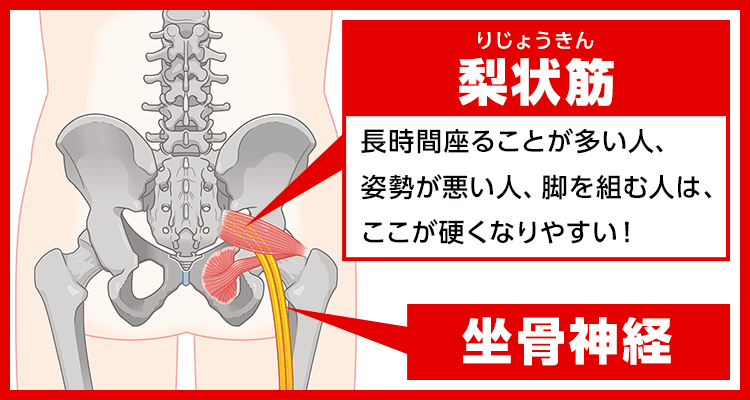

こんな痛みやしびれの原因は

梨状筋(りじょうきん)というおしりの奥の筋肉が硬くなること。

というのも

梨状筋のそばには坐骨神経が通っており、

梨状筋が硬くなると坐骨神経が圧迫されて傷ついてしまいます。

そして坐骨神経はおしり〜足先まで伸びているため、

損傷すると様々な箇所にしびれや痛みが現れるんです…

つまり、

これがしびれや痛みのメカニズム!

しかも残念なことに、

神経は一度損傷すると

自力で修復するのはほぼ不可能…